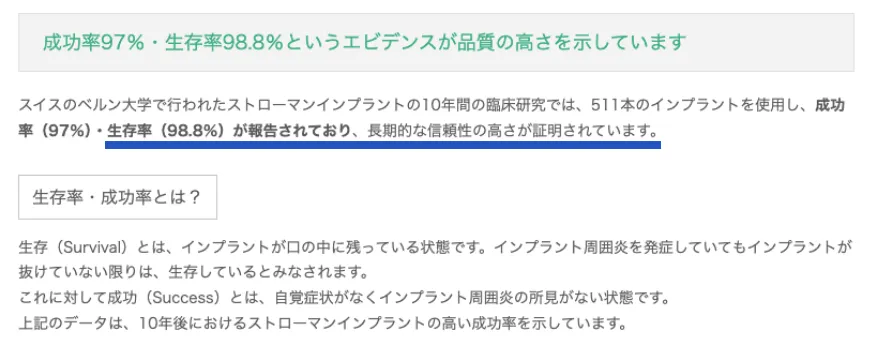

ストローマン社のインプラントが

10年後も使える確率は98.8%

引用元:https://straumannpartners.jp/medical/reason/trust/